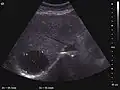

The ultrasound appearance is a well defined lesion, with very thin, almost unapparent walls, without circulatory signal at Doppler or CEUS investigation. The content is transonic suggesting fluid composition. The presence of membranes, abundant sediment or cysts inside is suggestive for parasitic, hydatid nature. Posterior from the lesion the acoustic enhancement phenomenon is seen, which strengthens the suspicion of fluid mass. They typically displace normal liver vessels but no vascular or biliary invasion occurs.

-

Liver cyst -